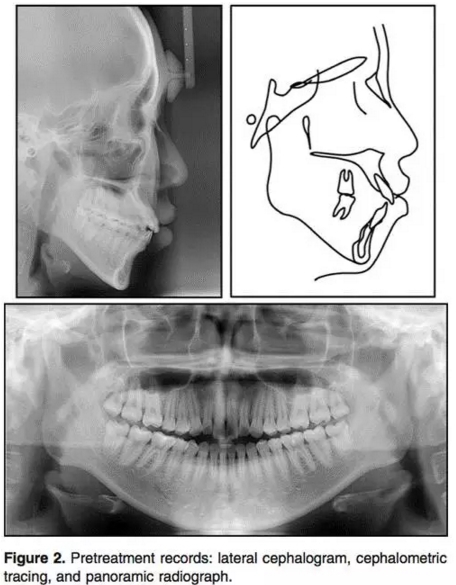

輔助檢查:側(cè)位片:骨性II類(ANB3.5°);下頜后縮(N per to Pog,-4.5°);高角(PFH/AFH, 59.5%; MP-FH, 32.7°)。上頜切牙輕微前突,下頜切牙突度正常(U1 to FH, 120.7°;IMPA, 90.0°)。上頜前后牙都垂直向發(fā)育過度(U1-PP, 36.9 mm; U6-PP, 27.9mm) 。上前牙在休息位時(shí)暴露量相對(duì)過量(U1 to stomion, 4.8 mm) 。咬合平面角正常(OP to FH, 12.8°)。此外,下頜垂直向高度也長(zhǎng)于正常值 (L1 to mandibular plane, 47.7 mm; L6 to mandibular plane, 37.0 mm;Table 1) 。